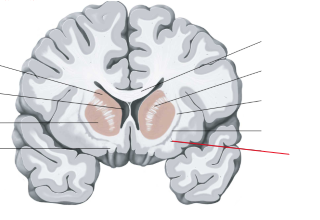

nucleus caudatus

putamen

globus pallidus

capsula interna (corona radiata)

capsula externa

capsula extrema

laterale ventrikels (I en II)

septum pellucidum